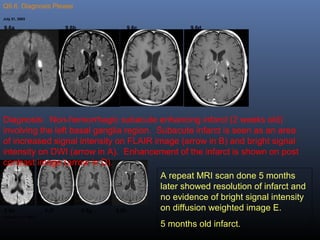

Q9.6. Diagnosis Please

July 31, 2003

T1-wtd imageDW Image FLAIR Image Post-contrast Axial T1-wtd

image

9.6a 9.6b 9.6c 9.6d

December 31, 2003

DW Image FLAIR Image T1-wtd image Post-contrast Axial T1-wtd

9.6e 9.6f 9.6g 9.6h

73 year-old male with stage IV non-small cell carcinoma presented with 2 weeks

history of sudden onset of speech difficulty with difficulty in word finding,

symptoms gradually improved. Clinical diagnosis: Stroke versus metastasis.

A repeat MRI

scan done 5

months later

Diagnosis: Non-hemorrhagic subacute enhancing infarct (2 weeks old)

involving the left basal ganglia region. Subacute infarct is seen as an area

of increased signal intensity on FLAIR image (arrow in B) and bright signal

intensity on DWI (arrow in A). Enhancement of the infarct is shown on post

contrast image (arrow in D).

A repeat MRI scan done 5 months

later showed resolution of infarct and

no evidence of bright signal intensity

on diffusion weighted image E.

5 months old infarct.